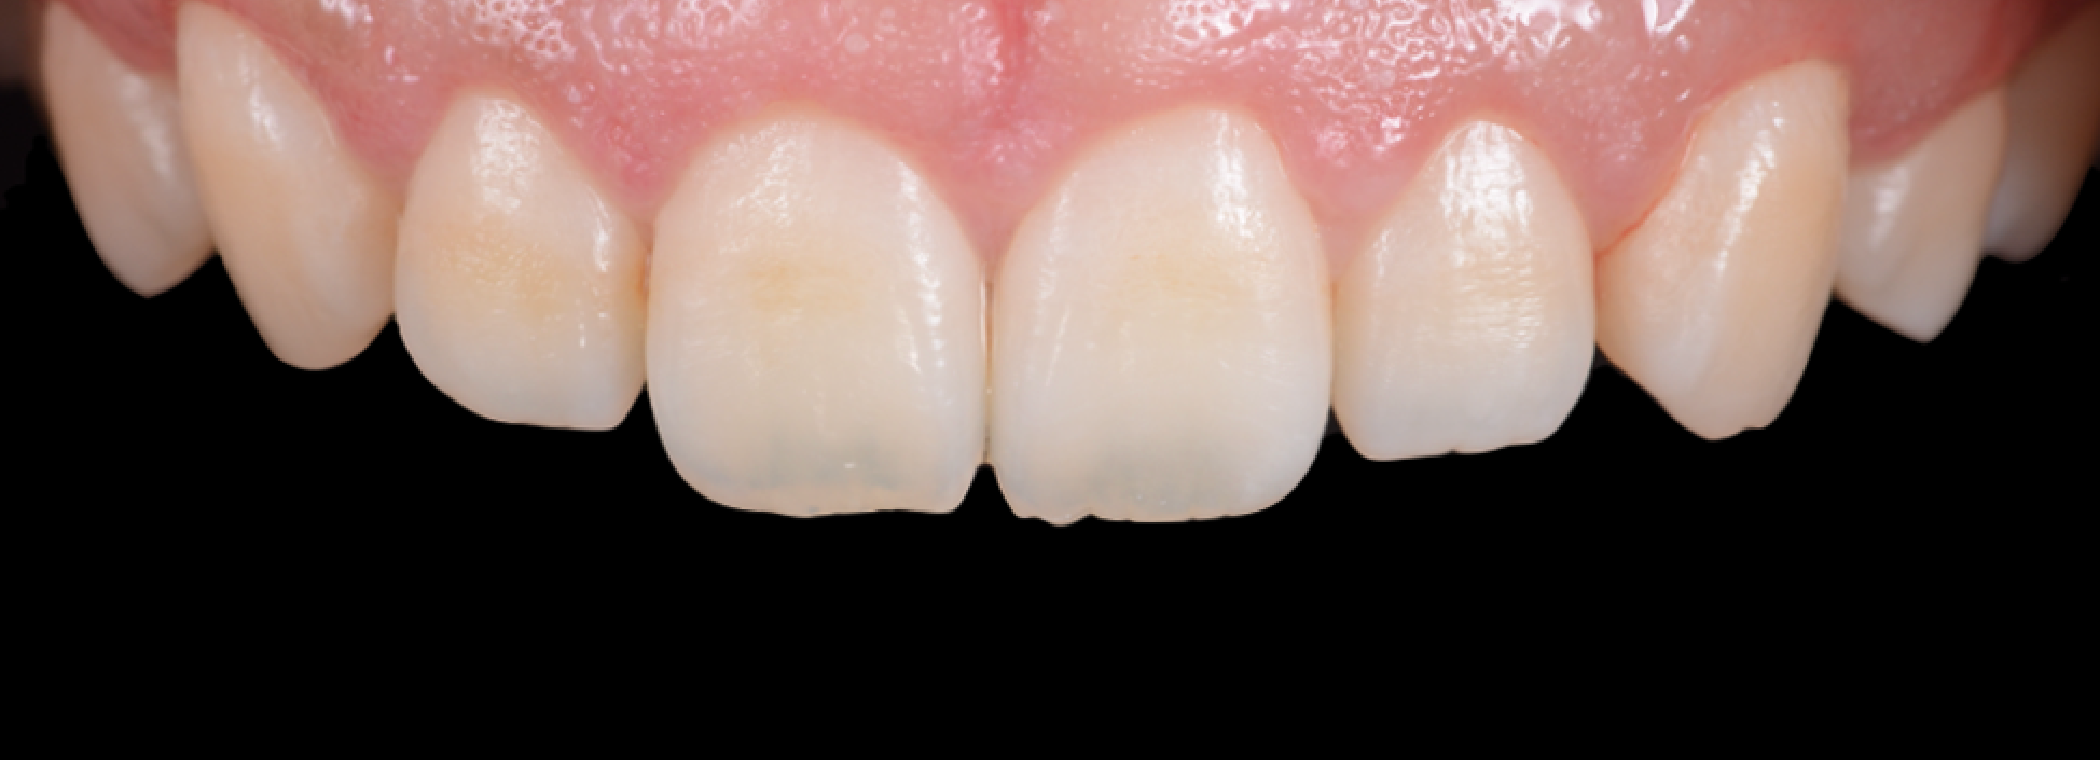

矯正治療の症例紹介

- 患者様情報30代 女性

- 来院動機歯並びが気になる

- 治療内容矯正治療

- 治療期間約2年

- 治療費用1,109,900円(税込)

検査費、治療費、月々の調整費込 - 治療のリスク歯肉退縮の可能性がある、装置装着の痛みを感じる場合がある